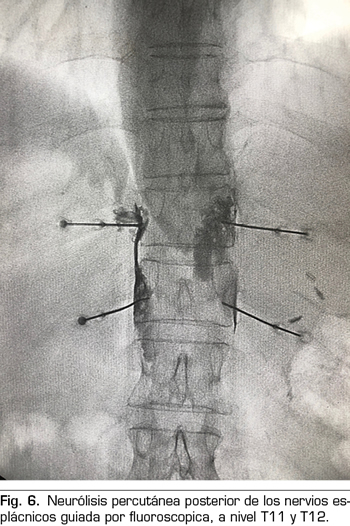

Se realiza mediante un abordaje posterior retrocrural, normalmente guiado por fluoroscopia (Figura 6). Las lesiones pueden llevarse a cabo mediante radiofrecuencia convencional o utilizando agentes neurolíticos como en el plexo celiaco.

Técnica percutánea